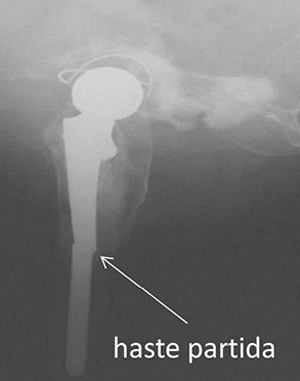

· FALÊNCIA DOS COMPONENTES

Na falência dos componentes metálicos ou cerâmicos, que é rara, mais comummente é a haste femoral que sofre a falência, que quebra. Muitas vezes nesta situação de falência de material o osso também sofreu fractura.

É necessário substituir o componente partido e muitas vezes há necessidade de proceder à revisão total, pois muitas vezes já não há material de próteses compatível com o que primariamente foi utilizado.